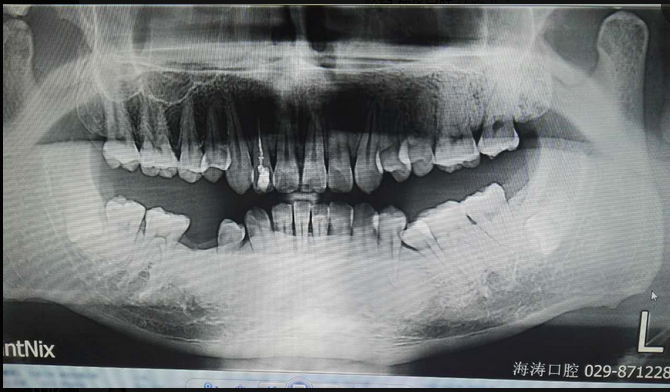

倒置阻生牙拔牙的病案討論

討論四:片子顯示的倒置阻生牙撥牙關(guān)健注意幾點(diǎn),1.翻瓣后去骨部位盡量離7遠(yuǎn)中,別破壞7遠(yuǎn)中骨壁,避免損傷7,以去除8根部的阻力為主。2.暴露阻生牙后,用鉆磨斷部分冠根后,用小骨鑿劈裂冠與根,可避免牙鉆因視野而誤傷神經(jīng)。3.冠根裂開后,先用牙挺挺出根部,然后挺出冠部。

提問(wèn):對(duì)7號(hào)牙沒(méi)有影響的埋伏智齒,是不是可以不拔?

答:一般情況下,完全骨埋伏阻生牙患者如無(wú)不適癥狀不會(huì)要求撥牙的,很多時(shí)候是口腔內(nèi)其它問(wèn)題拍片時(shí)發(fā)現(xiàn),但醫(yī)生發(fā)現(xiàn)這種情況要告知患者將來(lái)可能會(huì)發(fā)生什么問(wèn)題,例如頜骨囊腫,7號(hào)牙松動(dòng)等等,畢竟這個(gè)8號(hào)牙是潛在的病灶牙,究竟撥與不撥得讓患者作主,我們得盡到告知義務(wù)。往往最后決定撥這類牙的患者都是有各種不適癥狀的。

至于對(duì)7號(hào)牙暫時(shí)沒(méi)有影響的埋伏牙,不等于以后永遠(yuǎn)不影響。